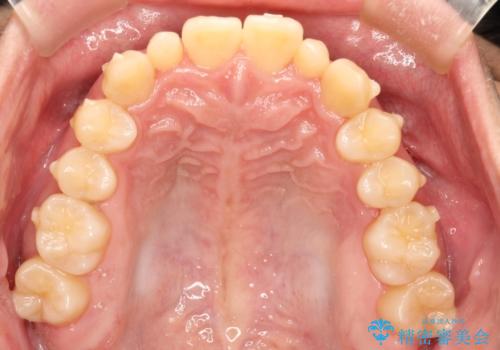

- 前歯のがたつきが気になるとのことで来院されました。

骨格的なところと、上下の歯の大きさのことを考慮して、下の前歯を1本抜歯し、インビザラインにて矯正治療することとなりました。

上の前から2番目の歯がもともと小さかったため、最後にかぶせ物を装着することで、自然な仕上がりにできました。